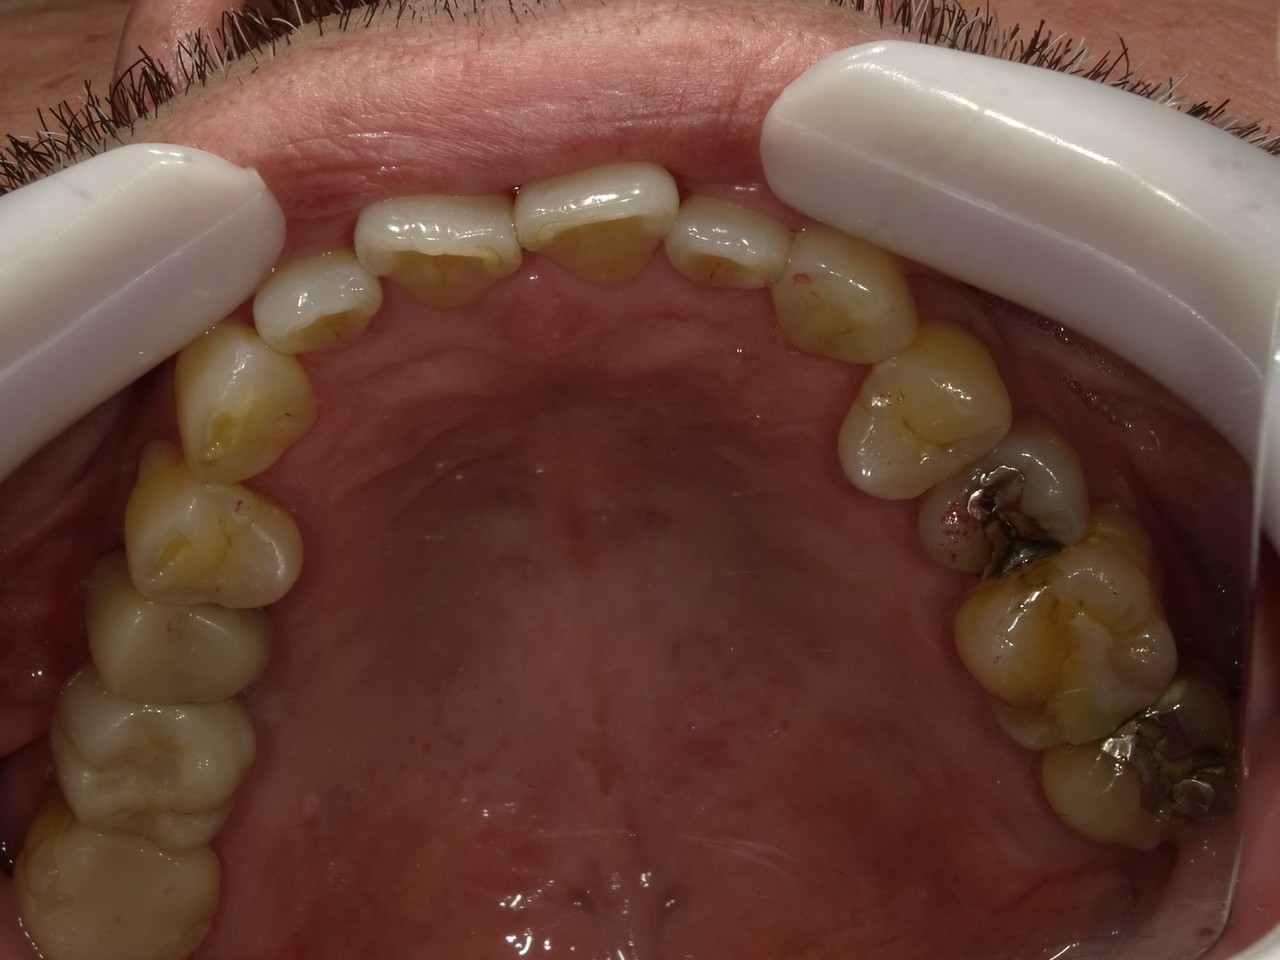

3.左上5の頬・舌側の大幅な骨欠損と上顎既存骨3mmまでの骨欠損がおこった症例に対しておこなったインプラント治療

Before

枚方市のインプラントの症例

I・K 様 女性 40代

症状としては、左上5の歯根破折を起こしていたため、排膿と自発痛をみとめた。それにともなう骨の大きな欠損。

治療法としては、炎症が強くたったためと、炎症による頬側側歯肉の退縮を認めていたために、まず、抜歯を行い上顎洞内及び歯抜した周囲組織の回復を試みた。その後、患者様がインプラント治療を希望したため、薄い上顎骨に対しては、グラフトレスサイナスリフト、骨欠損部には、人口骨補填を行い、頬側歯肉が退縮していることを改善するために、1回法でリーリングアバットメントを装着して、アバットメントの上に歯肉が覆うようにして、歯肉のボリューム回復を行った。2か月後、インプラントが骨と結合していることを確認して、光学印象を行い、2週間後にアバットメントとジルコニアクラウンを装着した。

治療結果としては、大幅な骨欠損があったが、グラフトレスサイナスリフトと骨欠損部に人工骨を補填して、抜歯した穴が自然に治る状態にしたことで、2か月半という短い期間での治療を完了することができた。(仮に、GBRや通常のサイナスリフトでの治療を行っていたら、最低でも1年は、かかってくる治療であると考える。)また、今回は、即時荷重を避け、1回法での治療を行ったことで、噛めない期間ができてしまったが、1回法で行ったことにより、歯肉のボリュームが増して、ブラッシングがしやすい口腔内環境にすることができた。低侵襲で、短時間で、治療を終えることができ、また、審美性・機能性の回復も行えたことができた。

治療の期間・回数:約2.5か月、6回

治療の価格:368,500円(税込)

治療費の内訳:インプラント基本料(フィックスチャー及び手術費用、投薬費用、レントゲン費用、インプラント上部費用(アバットメントおよびジルコニアクラウンの費用用)330000円(税込み)。オプション費用グラフトレスサイナスリフト費用プラス人工骨費用 38500円(税込み